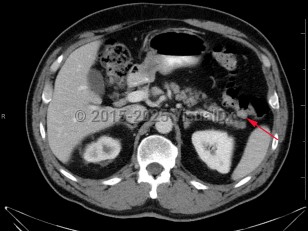

Colonic polyps

Histologically, polyps may be tubular, villous, or tubulovillous. Villous adenomas are 3 times more likely to become malignant than tubular polyps. The likelihood that a polyp contains invasive cancer increases with the size of the polyp. Most polyps remain asymptomatic and are detected during routine screening colonoscopy. Less than 5% of polyps lead to bleeding.